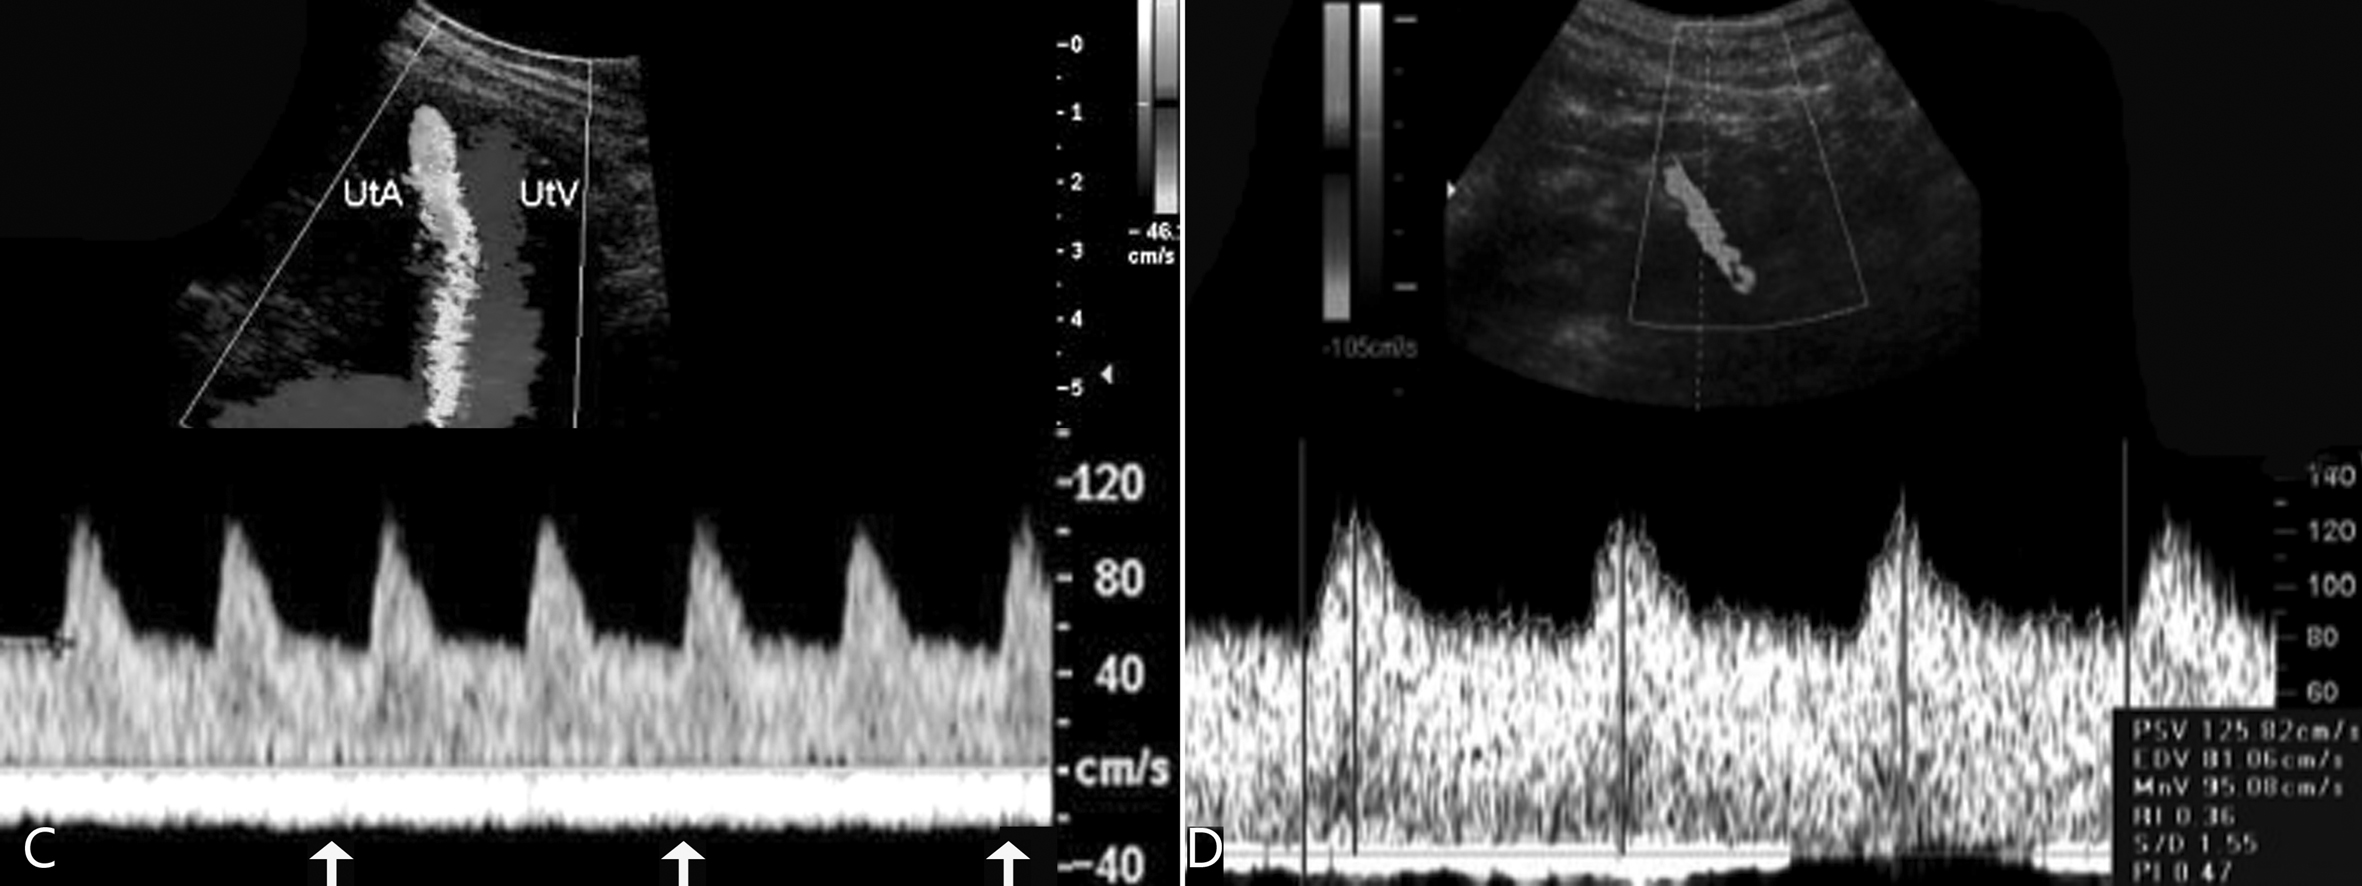

图4孕期子宫动脉血流变化

C:30周妊娠子宫动脉显示舒张期血流速度明显增加;箭头示子宫静脉持续、匀速的血流速度曲线;D:38周妊娠子宫动脉显示典型的低阻力型血流速度曲线

子宫静脉显示为低速、均匀的血流(图4C),随着妊娠周数的增加,也可发现其平均血流速度的增加。出现搏动性血流可能与不良妊娠有关。